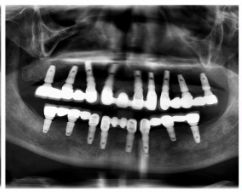

種牙前照片

通過X光片可以看到,醫(yī)生雖然盡量設(shè)計(jì)連冠種植,但還是用了十七個(gè)植體,盡管已經(jīng)是多次調(diào)整后的精簡(jiǎn)方案,但手術(shù)時(shí)長(zhǎng)依然長(zhǎng)達(dá)一天。位老先生之前在另一家醫(yī)院咨詢時(shí),醫(yī)生給的方案是種二十二個(gè)植體,光是種植費(fèi)用就令人大呼“害怕”了。